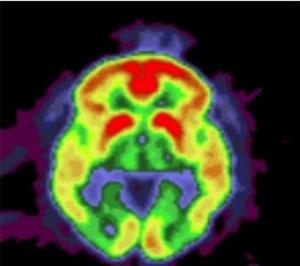

Sources: PLoS One, Feb. 1, 2012 doi:10.1371/journal.pone.0031039Rare variants in APP, PSEN1 and PSEN2 increase risk for AD in late-onset Alzheimer's disease families.et Washington University School of Medicine(Visuel Knight Alzheimer's Disease Research Center: L'image du cerveau montre une accumulation de dépôts amyloïdes (jaune et rouge) chez un patient ayant la maladie d'Alzheimer).